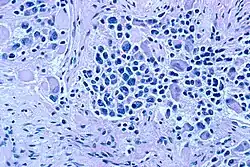

El diagnóstico se confirma por un patólogo quirúrgico, teniendo en cuenta la presentación clínica, hallazgos microscópicos, y otras pruebas de laboratorio. En la microscopía, las células tumorales suelen ser descritos como células pequeñas, redondeadas y de color azulado, con patrones de roseta (seudorosetas de Homer-Wright). Para la distinción histológica de los neuroblastomas de otras patologías similares como el rabdomiosarcoma, el sarcoma de Ewing, el linfoma y el tumor de Wilms se emplean una variedad de tinciones inmunohistoquímicas.